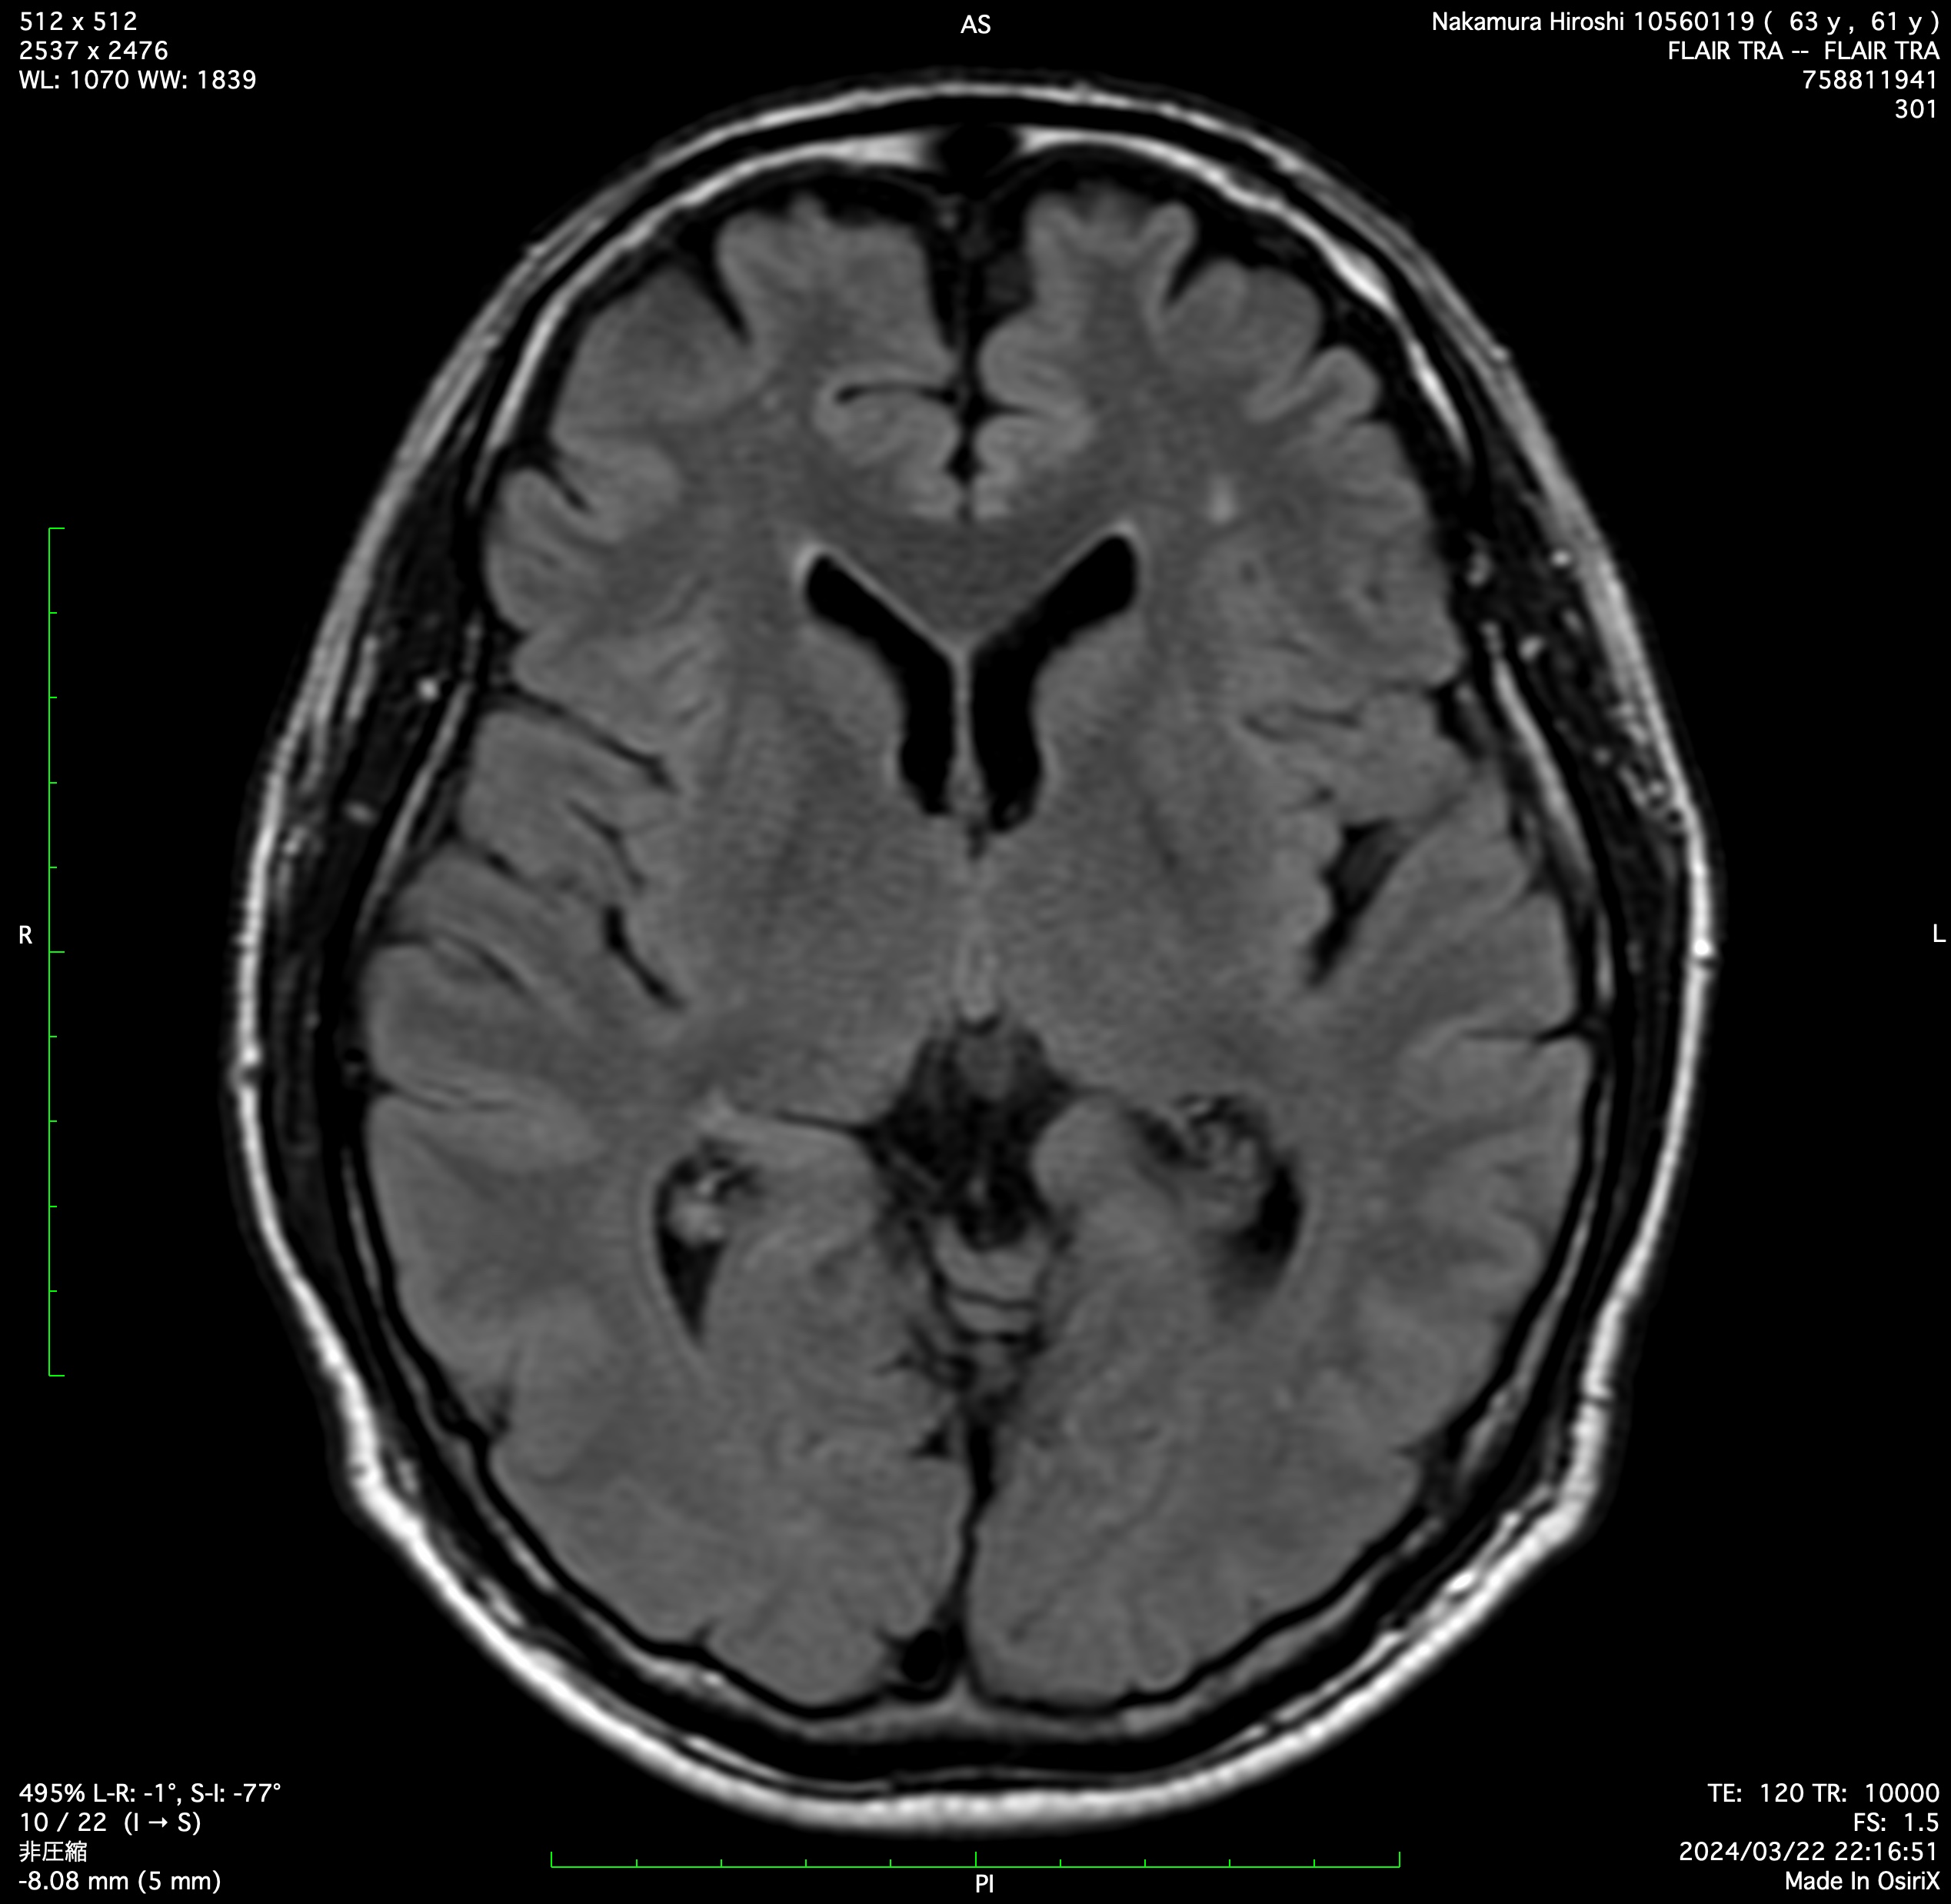

While a detailed examination of the brain is the foundation of our service, its true value lies in what it reveals about your body's overall vascular condition. The brain's delicate arteries are often the first place to show the subtle, silent progression of lifestyle-related diseases such as hypertension, diabetes, and dyslipidaemia. Our Brain Dock provides a clear visualisation of this impact.

A clear understanding of the current state of your brain's structure, including early signs of atrophy or risk factors for stroke such as cerebral aneurysms.